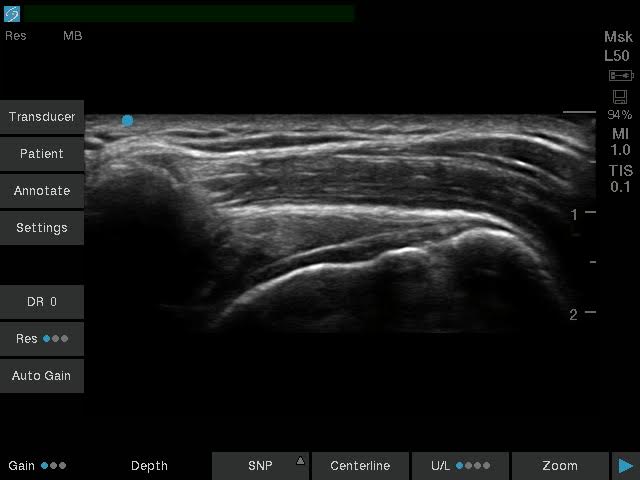

| کاربری | سونوگرافی و اکوکاردیوگرافی |

| کاربری | سونوگرافی و اکوکاردیوگرافی |